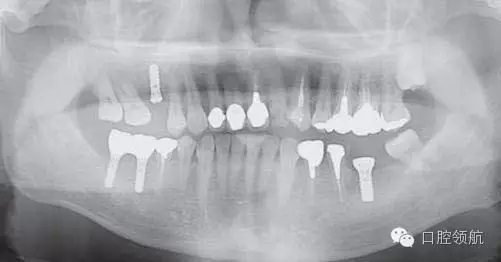

患者,38歲,男性,作為需要全面治療的患者來院?;局委熀?,右下頜磨牙區(qū)及右上頜磨牙區(qū),還有拔牙后的左下頜磨牙缺損區(qū),擬進行種植修復。圖1為初診時的曲面斷層影像,問診,模型診斷,曲面斷層檢查均未見異常,因此,最先在右下頜磨牙缺損區(qū),繼而在右上頜磨牙缺損區(qū)植入種植體,這些種植體愈合良好。

圖1 初診時的曲面斷層影像。